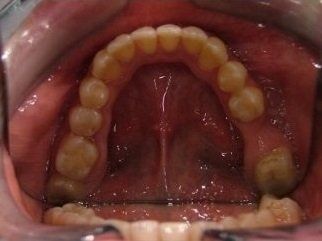

Il trattamento ortodontico non è solo per i bambini: se hai denti storti, affollati, mancanti o prominenti che ti impediscono di masticare e parlare liberamente, potrebbe essere necessario rivolgersi a uno specialista. L’ortodonzia prevede l'uso di apparecchi ortodontici, che possono essere fissi o rimovibili.

I dentisti studiano infatti le anomalie di costituzione, posizione e sviluppo di denti e ossa mascellari, e progettano l’apparecchio mirando al ripristino della corretta funzionalità dell'apparato masticatorio.